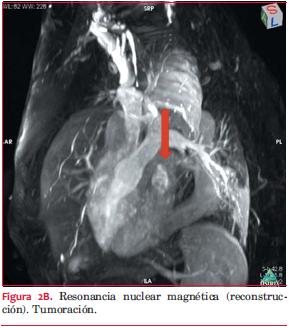

Resonancia nuclear magnética: derrame pericárdico severo. Pericardio normal. Tumor intrapericárdico de 36 por 32 mm, sólido, hipervascularizado, bien delimitado, con centro necrótico (figuras 2A, B y C).